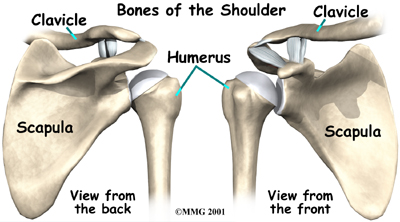

The shoulder is made up of three bones: the scapula (shoulder blade), the humerus (upper arm bone), and the clavicle (collarbone).

Shoulder Bones

As the arm is raised, the rotator cuff also keeps the humerus tightly in the socket of the scapula, the glenoid. The upper part of the scapula that makes up the roof of the shoulder is called the acromion.